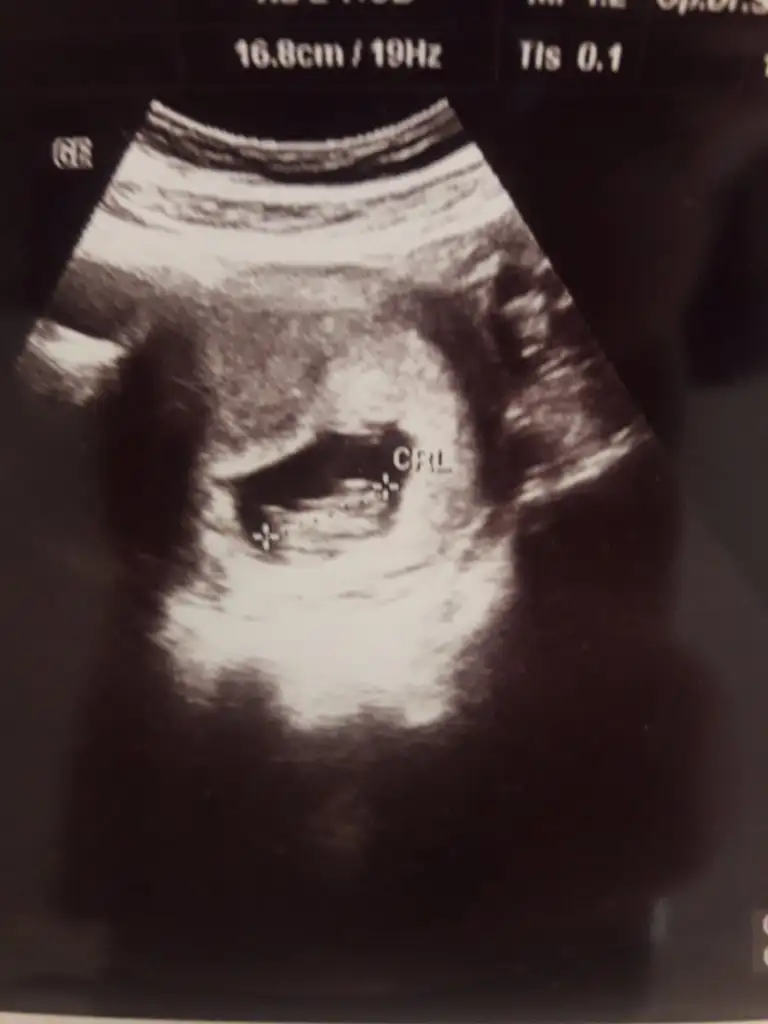

bana da bi tahmin yaparmısın. 10+2 karından bakıldı

prenses uzanmış12+1 karından ultrason. Doktor bi kıza benziyor dedi bi erkeğe sizde tahminde bulunur musunuz

5 ve 14. haftaya kadar olan ultrason fotolarınızı paylaşın. Vajinadan mı yoksa karından mı çekildiğini ve kaç haftalık olduğunu da mutlaka belirtin.